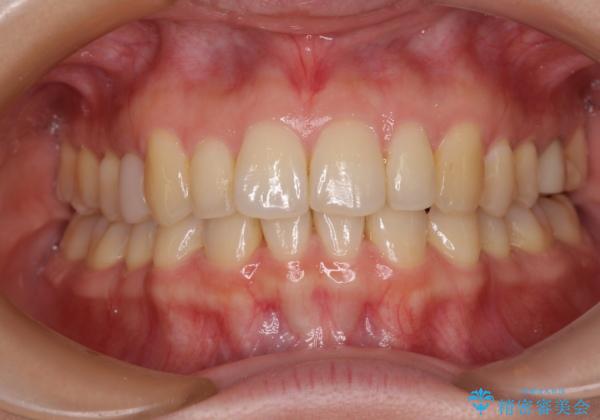

先天欠損のある歯列 インビザライン矯正

左右上顎側切歯2本が矮小歯であるため、上顎の抜歯ではなく、IPR(歯と歯の間を削る)と歯列全体の後方移動によってバランスを整えることとしました。

歯列のバランスが悪く、インビザライン矯正特有の奥歯の噛みにくさがなかなか改善されず、治療期間が長期化してしまいました。